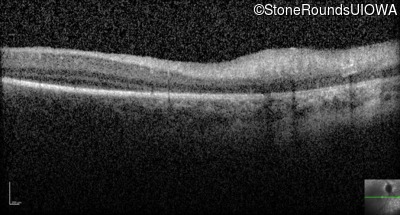

Optical Coherence Tomography - Right -

No Light Perception

Exemplar

Expanded OCT Stack

×